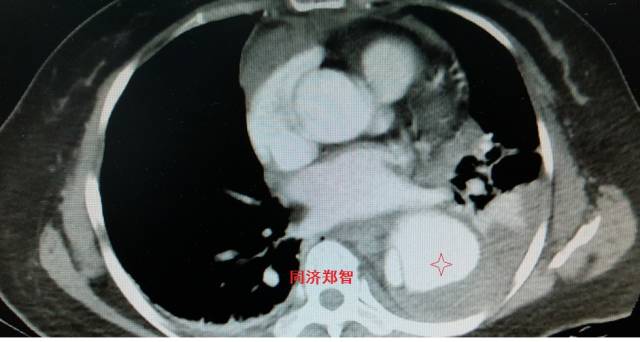

胸部平扫CT提示升主动脉增宽(红色星形标记),CTA证实A型主动脉夹层伴升主动脉夹层动脉瘤形成。

图3